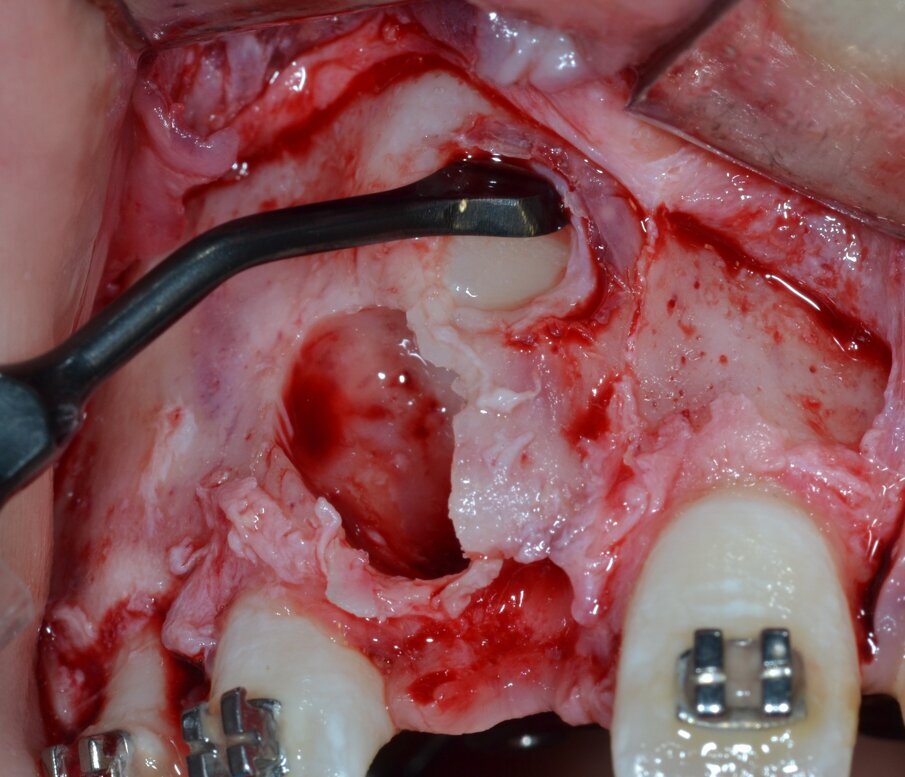

Dopo analgesia locale ottenuta per infiltrazione di Articaina cloridrato 40 mg con epinefrina 1:100.000 viene sollevato un lembo a tutto spessore (Fig. 4) per esporre la zona interessata dalla lesione e si procede quindi all’estrazione dell’elemento deciduo 5.1 (Fig. 5).

Fig. 4_Lembo a tutto spessore che espone la zona interessata dalla lesione.